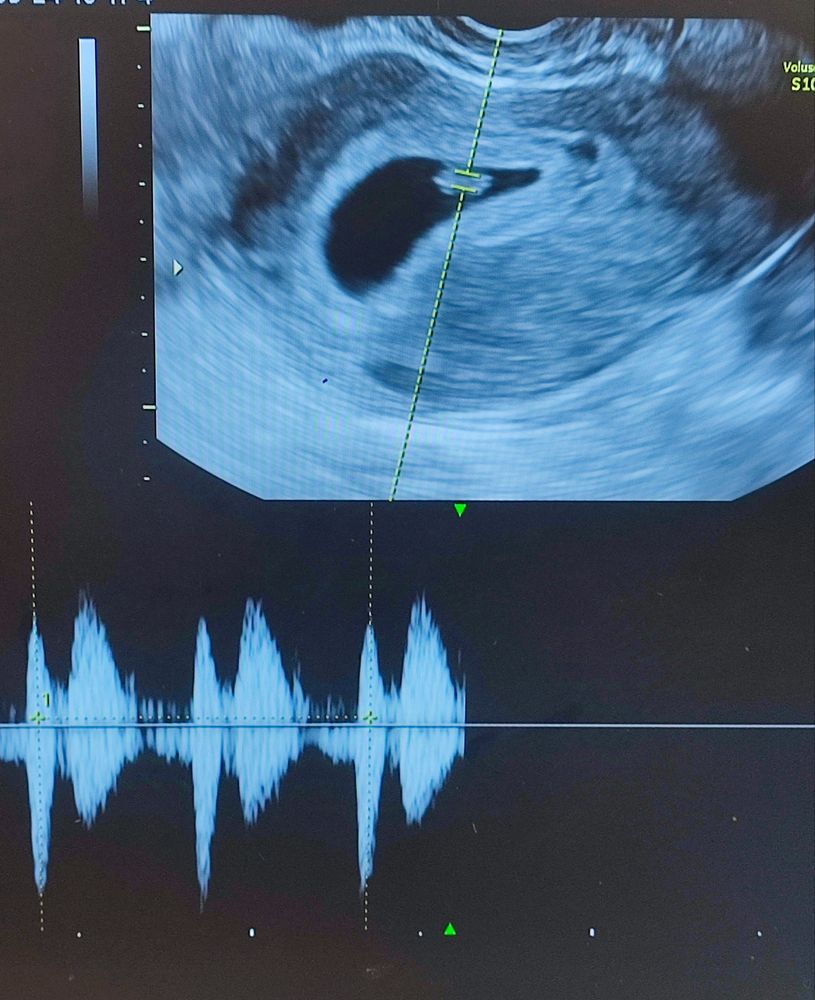

28 дпп. УЗИ.

Мария, 7,1 мм. В посте написано)

Екатерина, чёт пропустила я В принципе для 28 дпп нормальный размер, конечно на пару мм хотелось бы побольше, но все индивидуально, все детки по разному растут, тем более при таких маленьких размерах большая погрешность измерения.

Как хорошо! Растите крепенькими✨️ Интересно, у вас же тоже перенос 13го сентября был? У меня сегодня тоже 28 дпп, и вчера было ровно 6 недель по месяч, я тоже ходила на узи. Получается, наверное, мне раньше перенесли🙄

Энни, спасибо! У меня по месячным 6,3 сегодня, перенос был на 17 ДЦ. Мне и так казалось, что рано. А у вас, видимо, ещё раньше, да

Энни, по УЗИ да, чуть больше, но по переносу 6,5 сегодня. А репродуктолог в вскр 5.2 по переносу поставила)). Короче, путаница с этими сроками.

Юлия Мать Драконов, да, спасибоооо. Теперь валяюсь, глушу тошноту крекерами с розмарином и пытаюсь работать. А на душе так радостно. Я даже видео короткое сняла, а на нем видно, как сердечко сокращается)